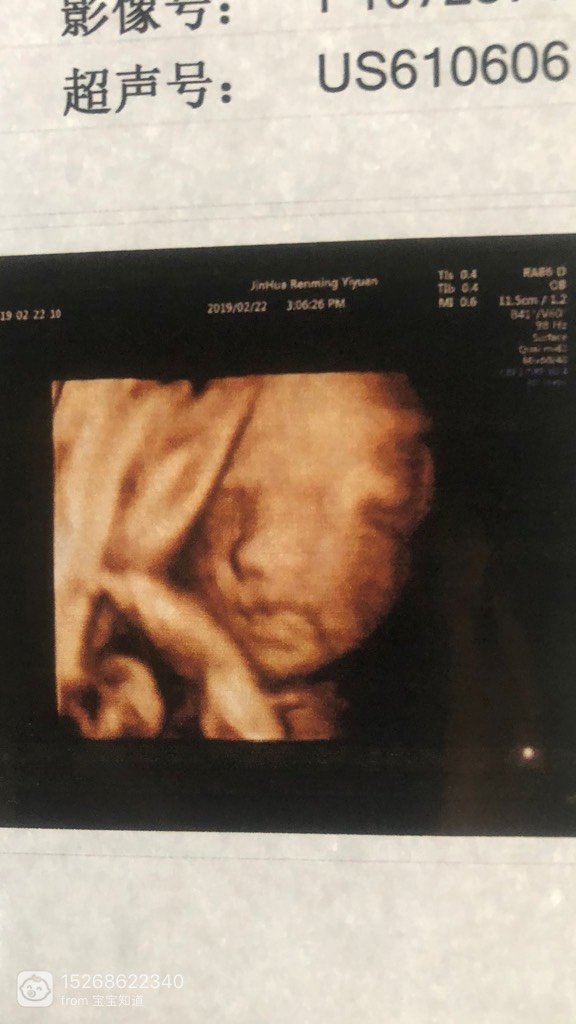

今天下午 去做产检宝宝在妈妈的肚子里很吵哦

今天乐剪下午 去做室生产检 宝宝在妈剪辉抹妈的肚子里 很吵哦